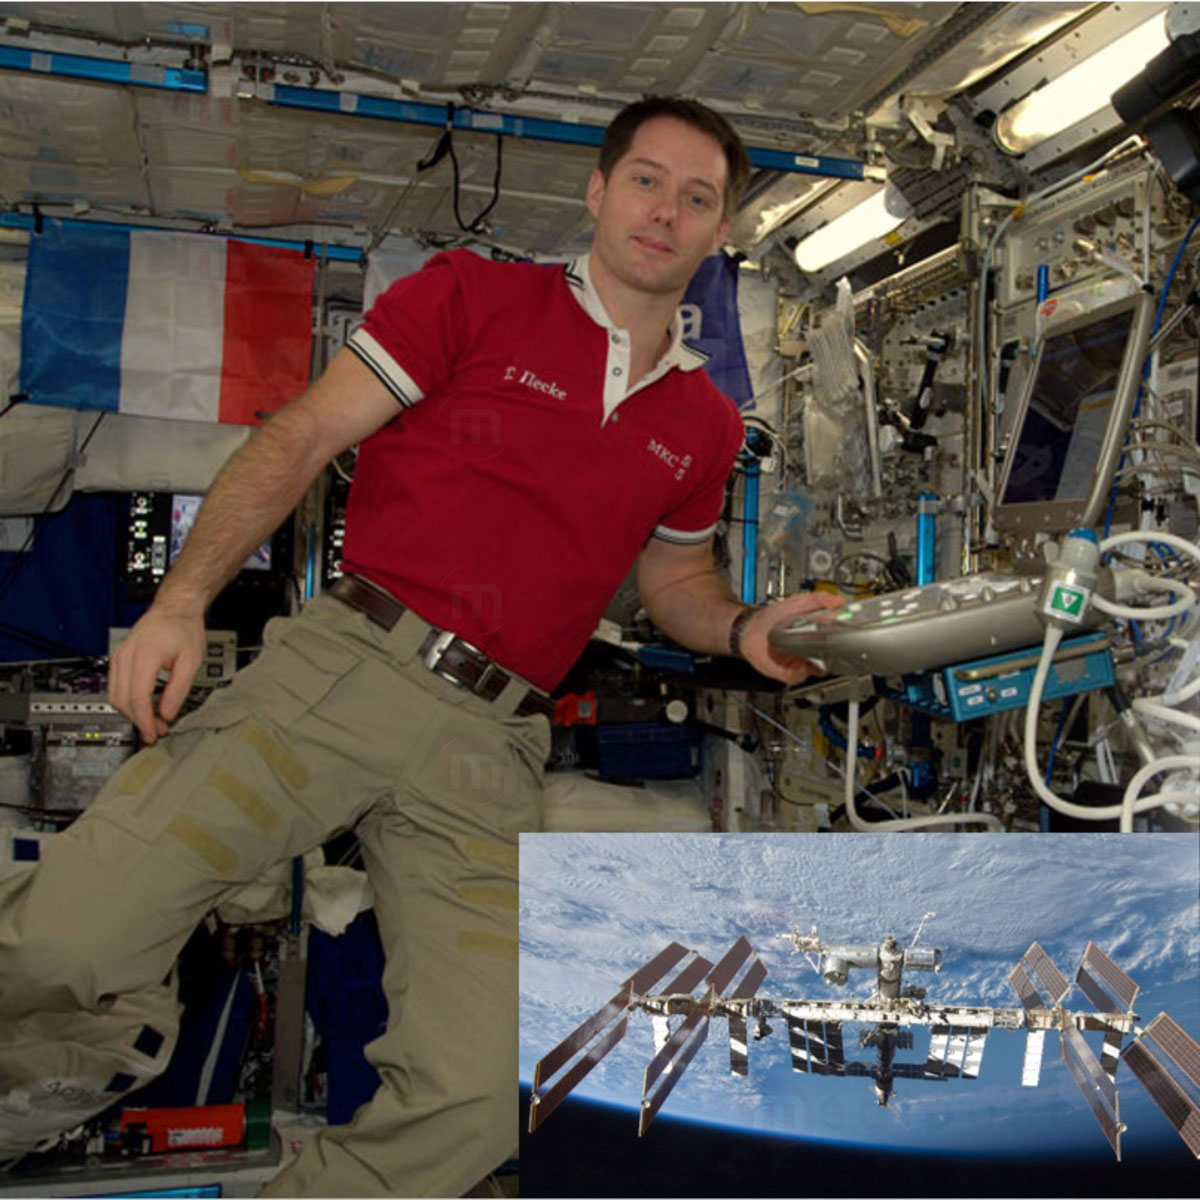

Echographe HD Sonoscanner Orcheo Lite

Orcheo Lite, c’est la polyvalence et la performance où que vous soyez.

Bénéficiant des modes d’imagerie les plus avancées (THI, Compound Imaging, Power and Directional Power…), l’Orcheo Lite est la réponse à vos exigences les plus pointues sur de multiples applications cliniques.

Son interface conviviale et simple d’utilisation fait accéder l’imagerie à ultrason à un nouveau degré de productivité en vous permettant de réaliser des examens plus rapides et plus sûrs.